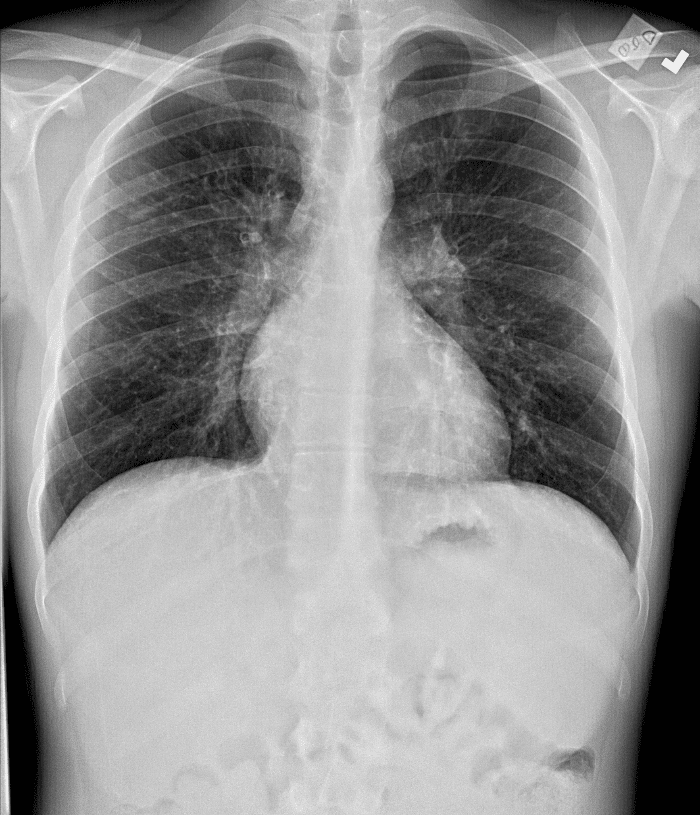

Practice Cases